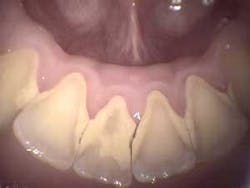

What should be photographed and reviewed with a patient? Items that should be documented in the digital patient record fall in this category. These include areas of visible pathology such as bruxism (Fig. 2), abfractions, attrition, caries, broken teeth, failed restorations, failed sealants, fracture lines, periodontal conditions including plaque, calculus (Fig. 3), root exposure, irregular or infected gum tissue, and soft-tissue lesions. It also is beneficial to take photos of normal teeth and tissue to show a patient the difference. A full-face portrait and full-smile photo also should be taken with a digital extraoral camera and imported into a patient’s file. These are helpful when discussing esthetic concerns, to have a baseline to compare to in the future, or for reconstruction in the unfortunate event that a patient loses part of his or her smile in an accident.

The most effective scenario is for a presentation to be divided into several categories by discipline: periodontal conditions, bruxism-occlusion, endodontics, basic restorative, and crown and bridge. A dentist or staff member might begin by watching a short video clip on periodontal disease with the patient. Following this, the patient can view intraoral photos showing the recession, tartar, and infection of his or her teeth and gums plus radiographs showing bone loss and tartar spurs. After seeing these problems in his or her mouth, the patient might be mortified initially. But soon the patient understands the situation, and is willing to discuss treatment. Once a patient understands the problem, he or she becomes concerned, and wants to know if the condition can be treated. The scaling and root planing now make sense, and the patient wants the treatment performed as quickly as possible.